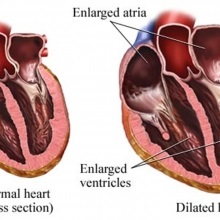

a) hasadék artériás légcsatorna A gyümölcs kapcsolat van között az aorta és a bal arteria pulmonalis (Batalla légcsatorna). Közvetlenül a szülés után a csatorna általában zárva van, de ha mégis, azt mondják, hasadék artériás vezeték. Ez a hiba gyakori uszkár, collie juhászkutya. Tüneteket.